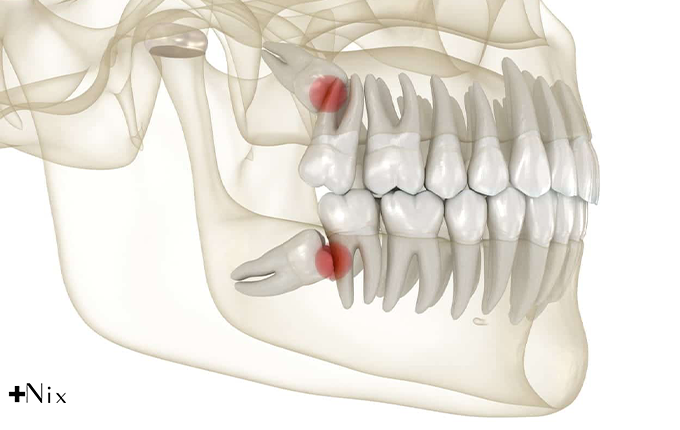

دندان عقل یا مولر سوم آخرین دندانی است که معمولاً بین ۱۷ تا ۲۵ سالگی در دهان رشد میکند. از آنجا که رشد این دندان دیرتر از بقیه دندانها آغاز میشود، در بسیاری از افراد فک فضای کافی برای رشد کامل آن ندارد.

به همین دلیل، رشد دندان عقل معمولاً ناقص است و دندان بهصورت نیمهنهفته یا کاملاً نهفته در لثه میماند.

مشکلات رایج دندان عقل

وقتی فضای فک محدود باشد، دندان عقل به دندانهای مجاور فشار وارد میکند. این فشار درد شدیدی ایجاد میکند و گاهی باعث جابهجایی دندانهای دیگر میشود. در چنین شرایطی، لثه اطراف دندان ملتهب میشود و احتمال عفونت افزایش مییابد. باقیماندن ذرات غذا و باکتریها در این ناحیه باعث ایجاد التهاب، کیست یا آبسه میشود. در برخی موارد، رشد ناصحیح دندان ممکن است به استخوان فک و دندانهای کناری آسیب برساند.